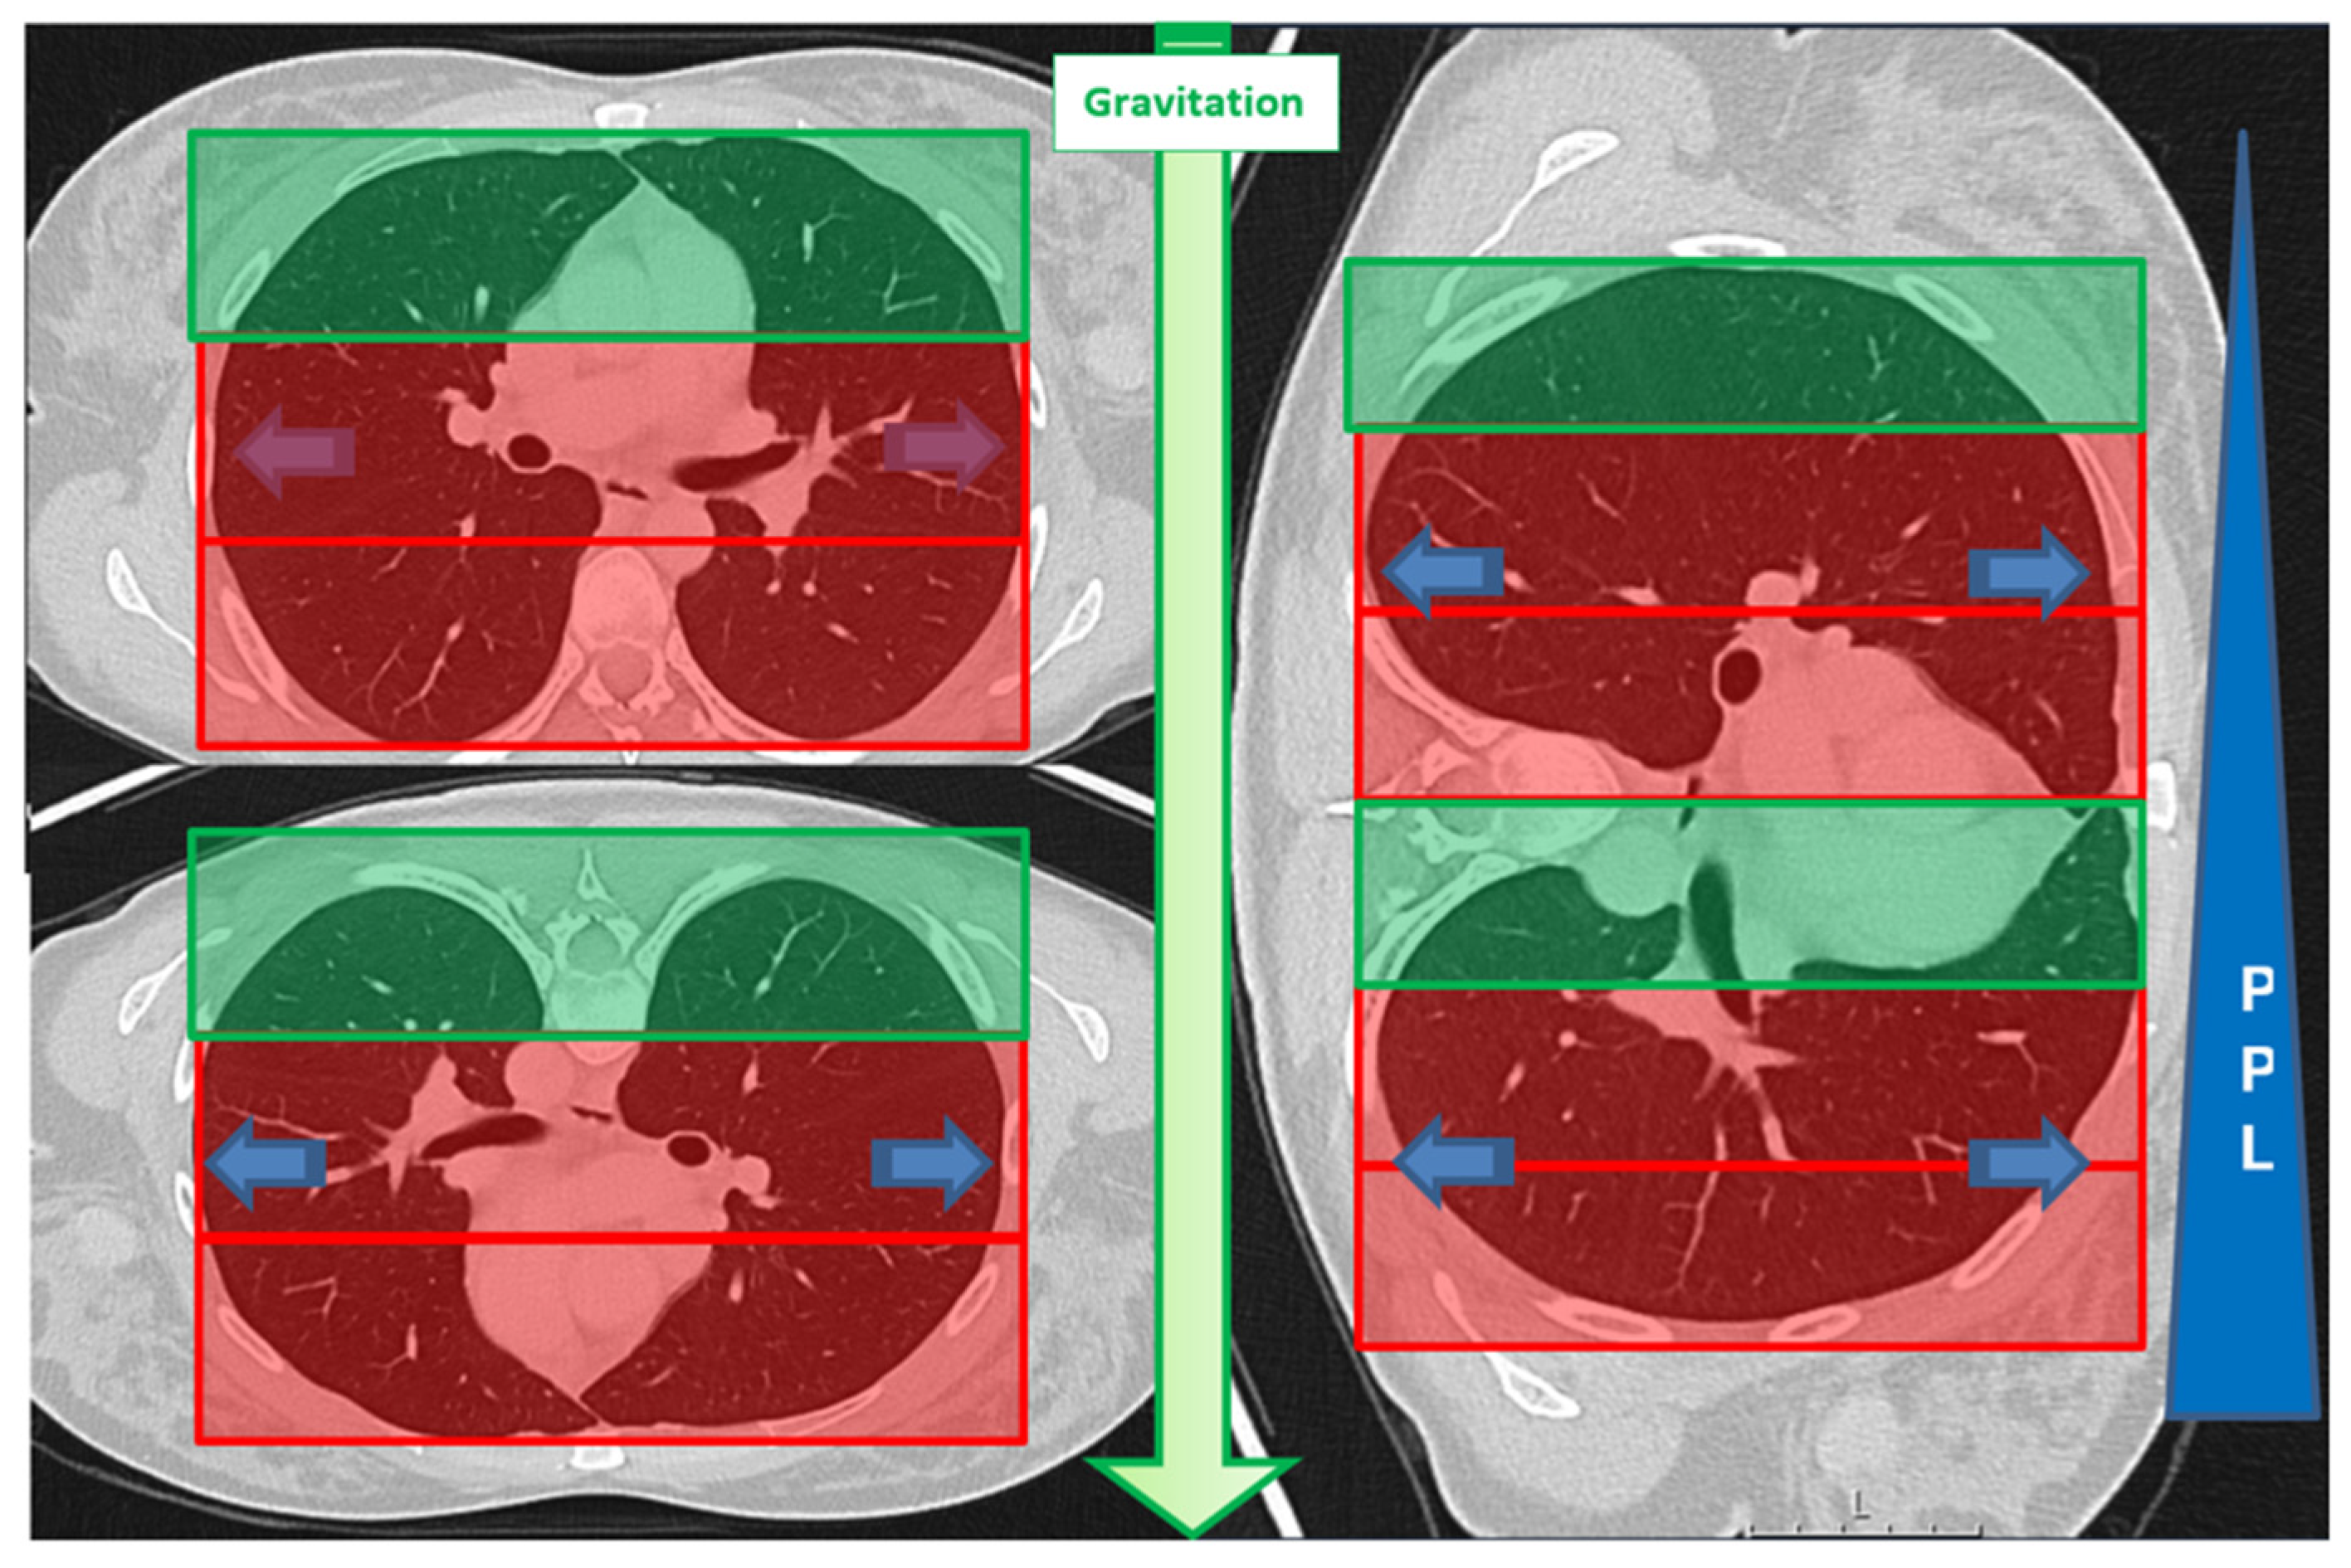

| Lesion location in D area | 53 | 46% | 34 | 40% | 19 | 63% | 0.034 * |

| Lesion location in D area | 1.402 | 0.517 | 7.369 | 1 | 0.007 * | 4.064 | 1.477 | 11.186 |